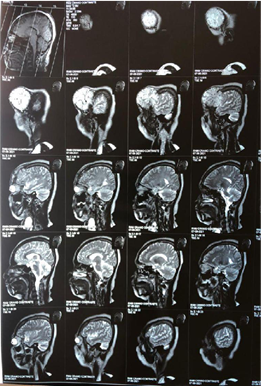

Figure 4A Contrast-enhanced magnetic resonance image showing a tumor in the extraaxial region of left frontal involvement in sagittal section.

Figure 4B Contrast-enhanced magnetic resonance imaging showing a tumor in the extraaxial region of left frontal involvement in coronal section.

Figure 3A Contrast-enhanced magnetic resonance image showing a tumor in the extraaxial region of left frontal involvement

Figure 3B Contrast-enhanced magnetic resonance imaging showing a tumor in the extraaxial region of left frontal involvement in coronal section.